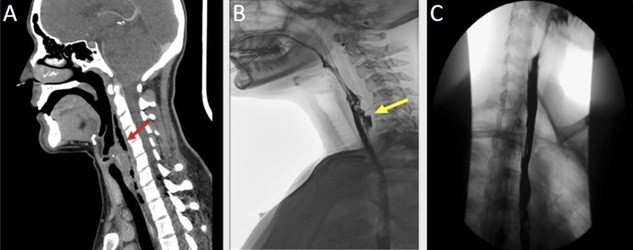

НемедицинаFigure 1. : A: Компьютерная томография (КТ) шеи, на которой видны газ и жидкость в заглоточном пространстве (указано стрелкой). B: Рентгеновская эзофагограмма с пероральным контрастированием, на которой видна утечка контрастного вещества в задней части дистального отдела глотки и проксимального отдела пищевода с экстравазацией контрастного вещества в задней части (указано стрелкой). C: Рентгеновская эзофагограмма с пероральным контрастированием, на которой не видно утечки контрастного вещества в шейные околопищеводные ткани спустя 2 недели